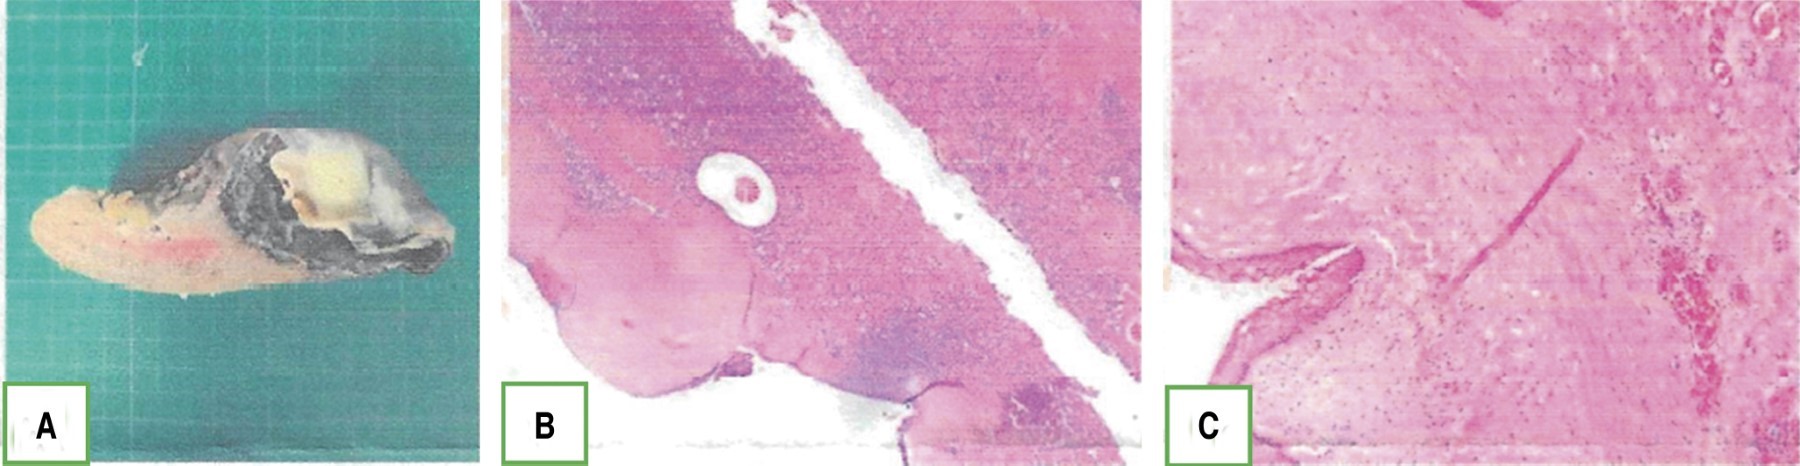

En el reporte histopatológico se describe bazo de 15 × 6 × 5 cm con quiste epidermoide (epitelio escamoso estratificado no queratinizante) de 8 cm con superficie interna trabeculada (Figura 6).

Esta anomalía puede presentar patologías intrínsecas al órgano como los tumores quísticos. Se clasifican en parasitarios y no parasitarios, estos últimos se dividen en quistes verdaderos; con revestimiento trabeculado epitelial epidermoide, transicional o mesotelial, y pseudoquiste, cuando carecen de él.3 Los quistes verdaderos son causados por un defecto en la migración mesotelial causando atrapamiento del mesotelio peritoneal en los surcos esplénicos. Las células epiteliales suelen ser positivas para CA 19-9 y antígeno carcinoembrionario, pudiendo elevar estos marcadores de manera sérica, sin representar potencial de malignidad, observándose un revestimiento liso de color blanco o gris y contenido líquido de características variables. Suelen ser asintomáticos, a excepción de quistes grandes que producen sintomatología por compresión a órganos adyacentes.3